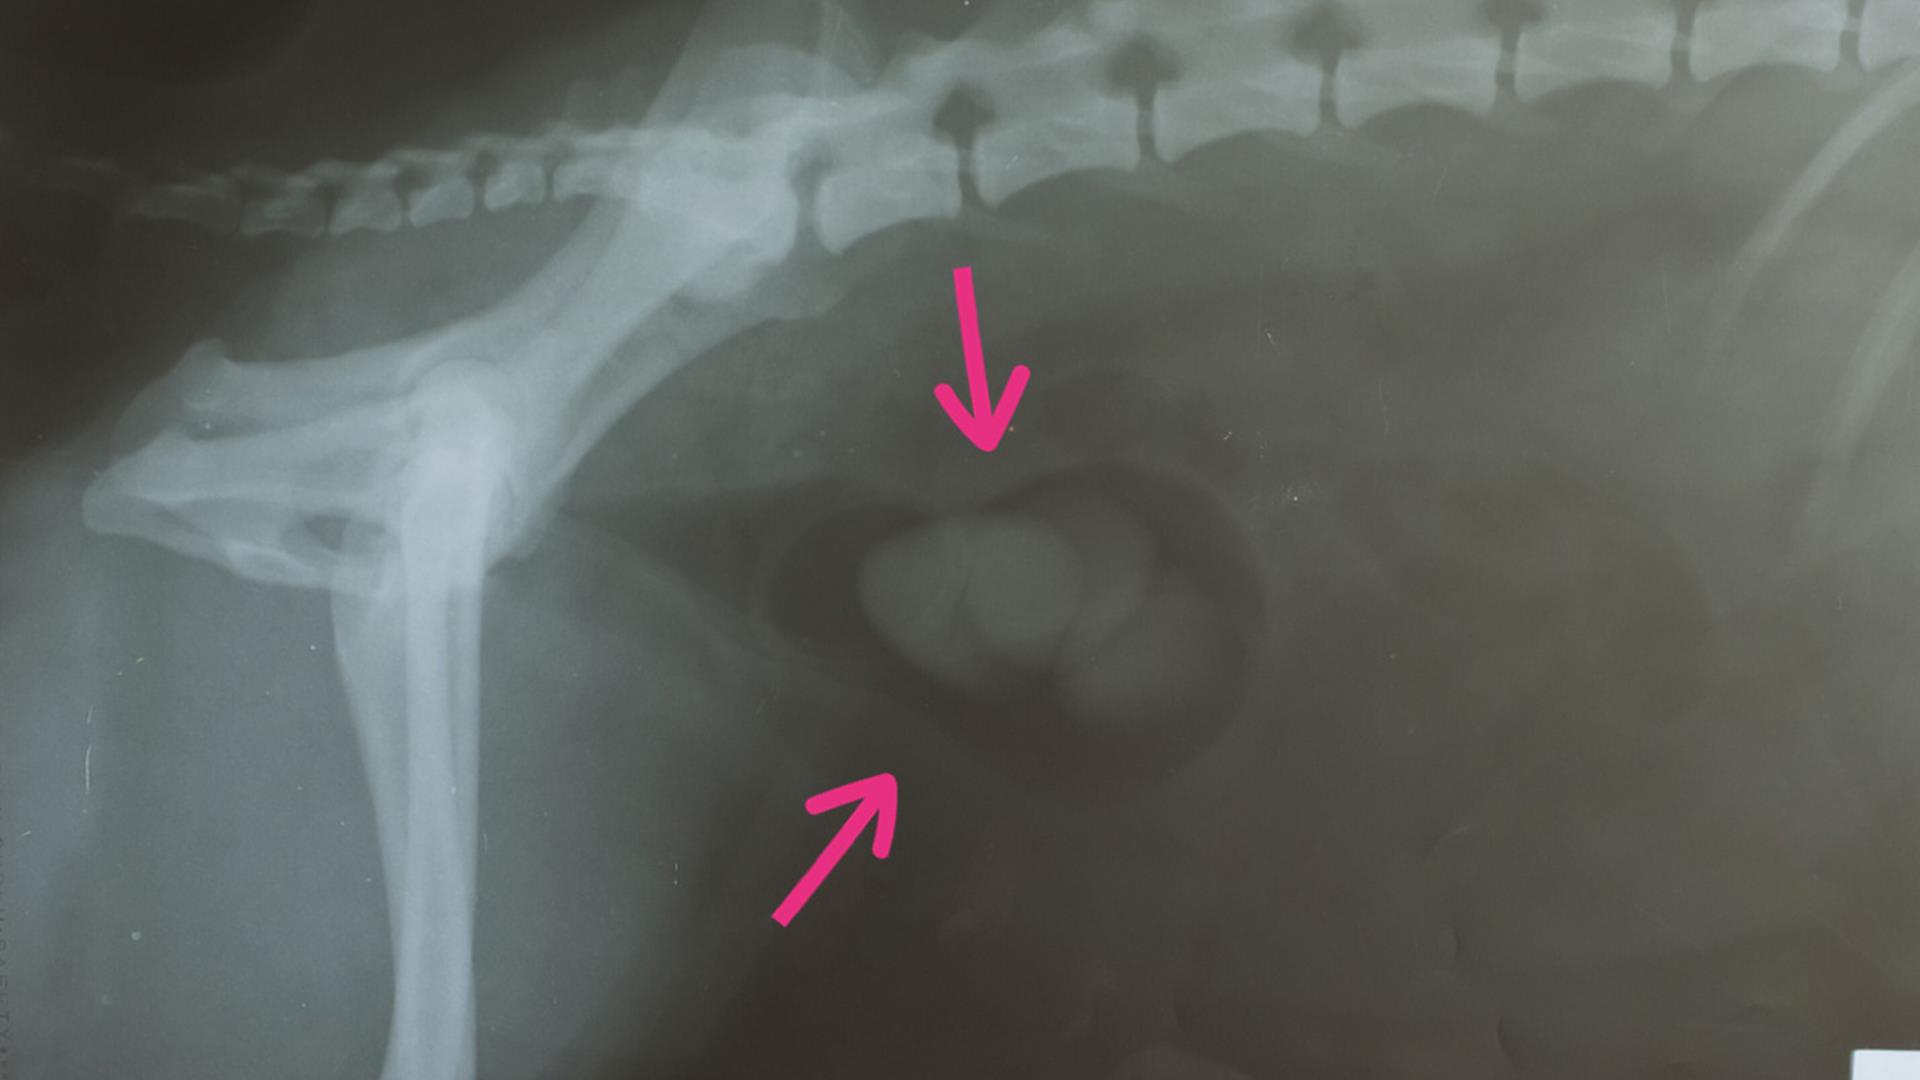

Your vet will ask you some questions about your dog and will feel your dog’s tummy. If they have large bladder stones your vet may be able to feel them, but it’s likely that they will need to carry out further tests, such as X-rays or an ultrasound of the bladder to confirm. A special dye is sometimes injected into the bladder to make the stone appear bright on x-rays.